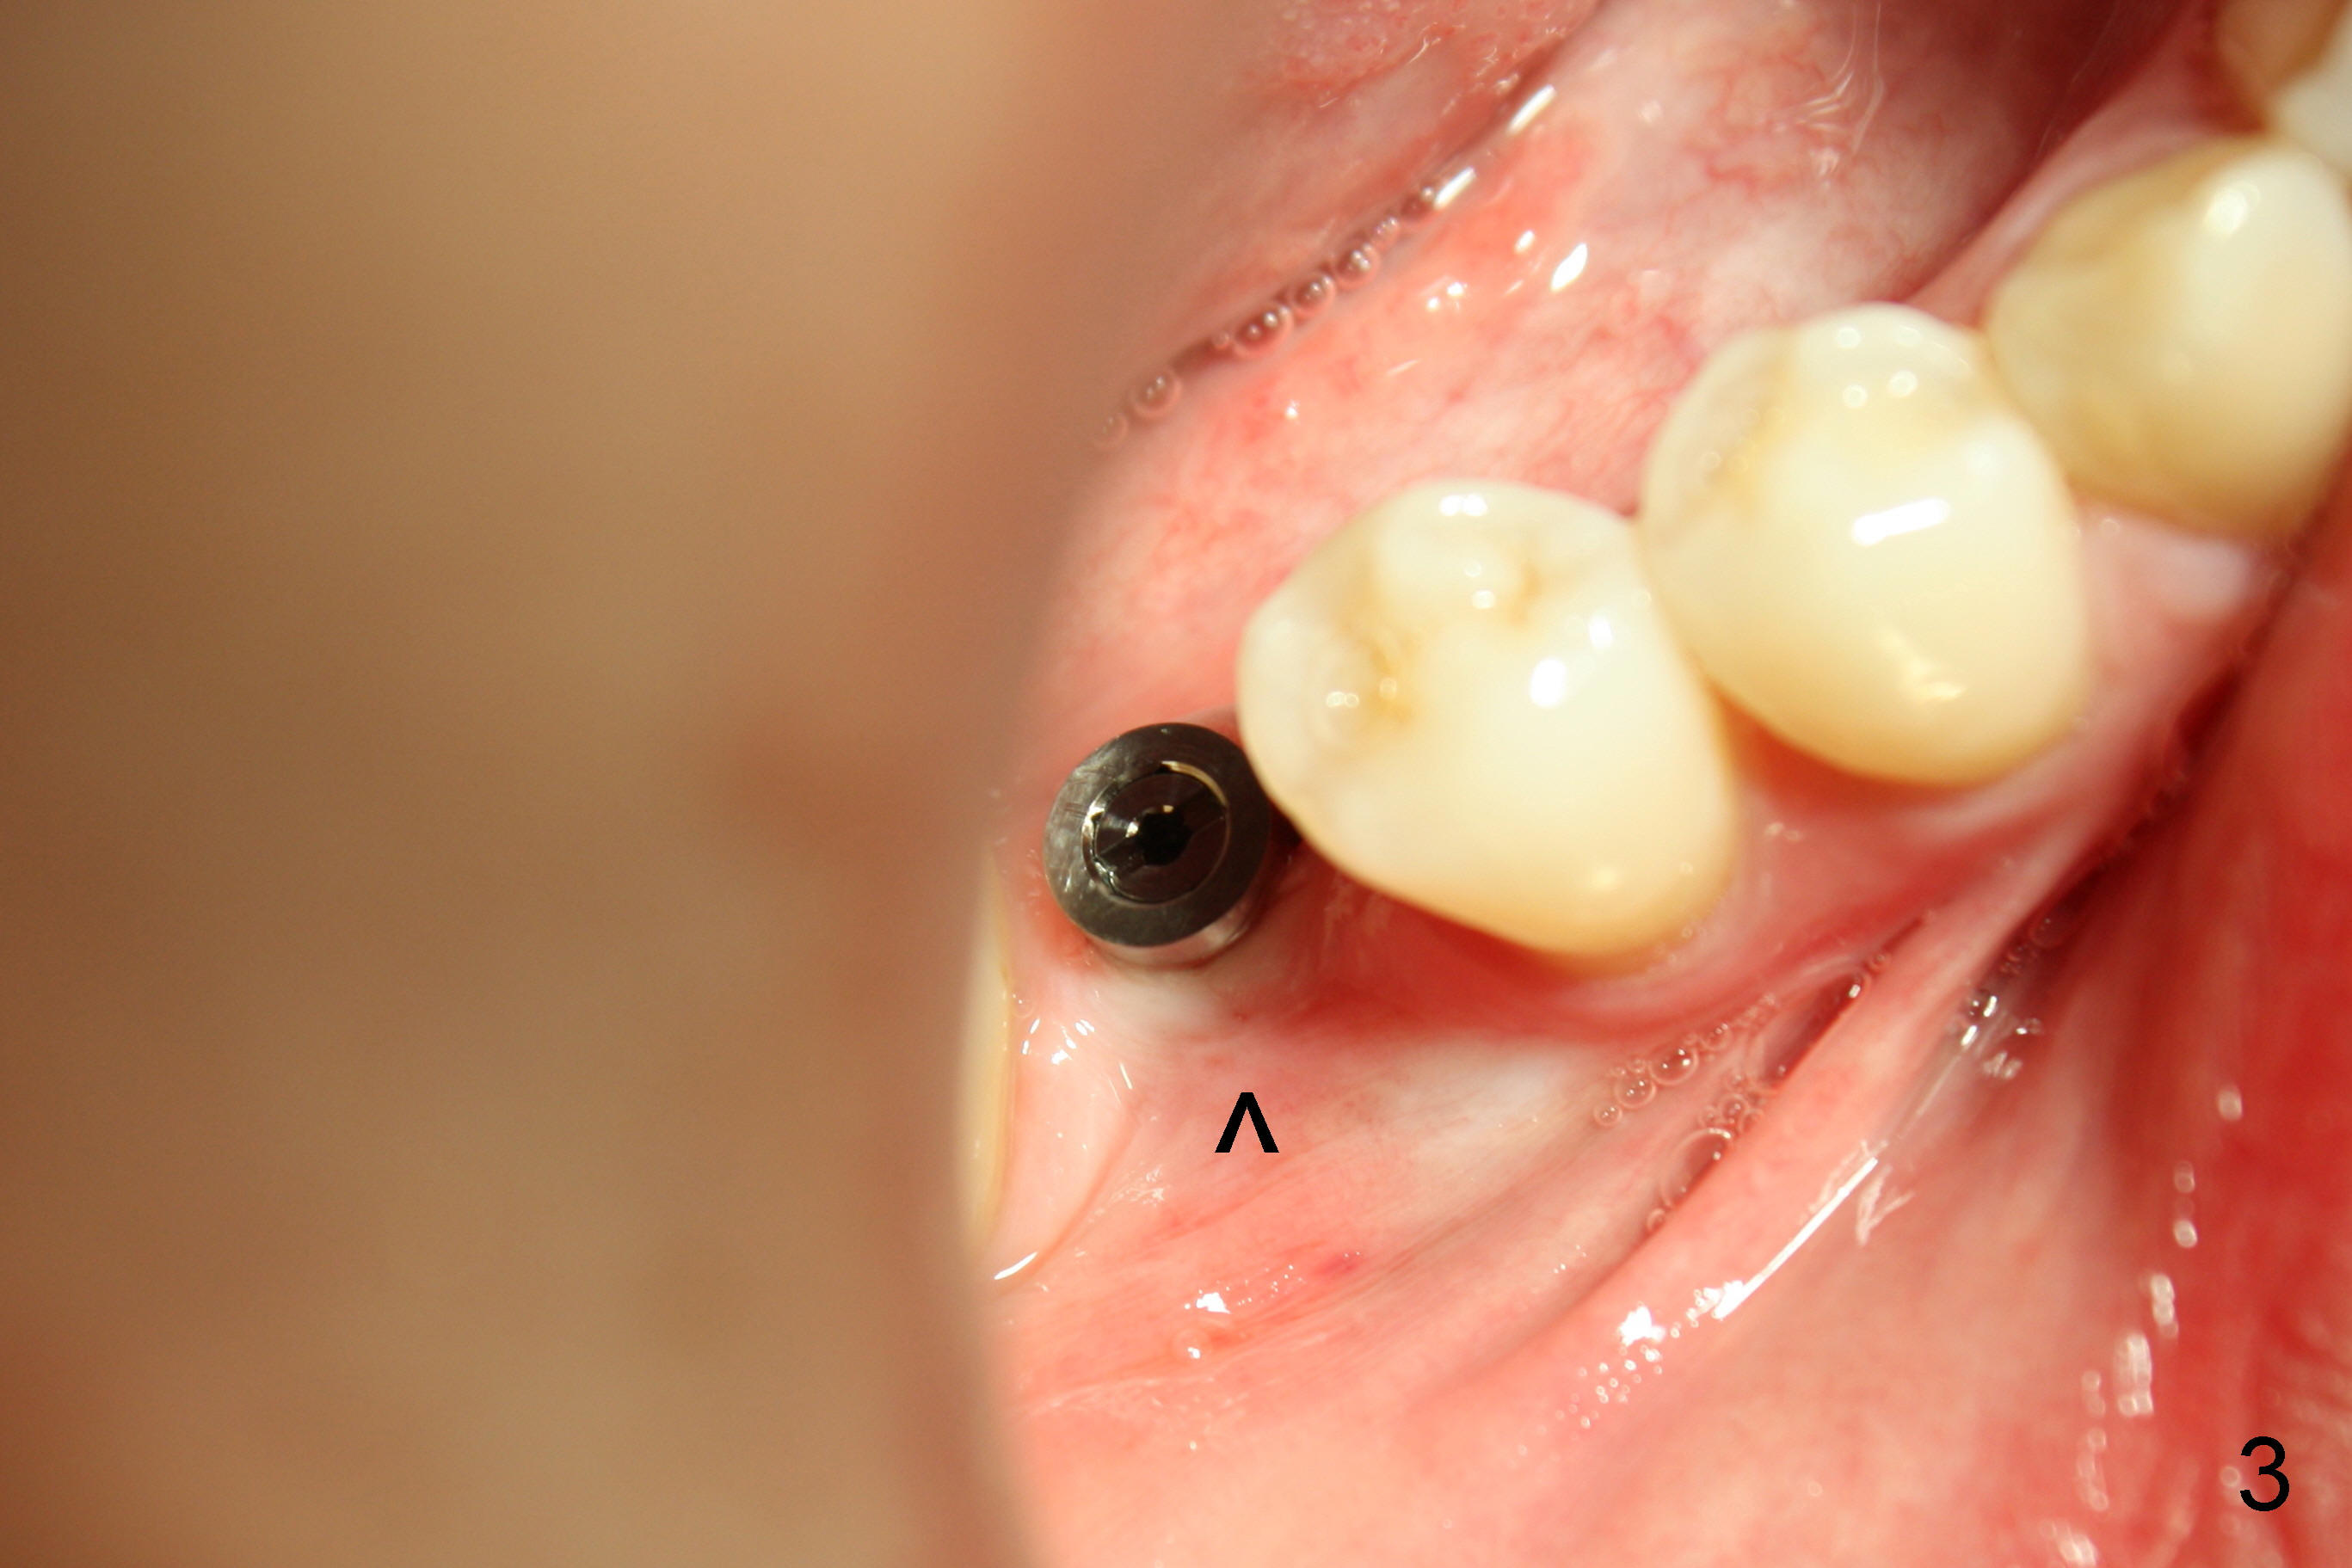

植牙不太容易,由于骨质缺损,植牙小些:4.5x17 mm,可能够用。几个月后病人回来,植牙愈合正常(图三,四,不过颊侧骨质凹陷,箭头),预约几周后修复。当她再回来做修复时,突然主述左上第一磨牙疼痛,需要做根管治疗,牙冠,老公满口同意,这时我们可以吃豆腐了(左上做牙冠,解决那里牙齿过分萌出问题(supraeruption)),不知他们这时怎么那么感慨解囊。